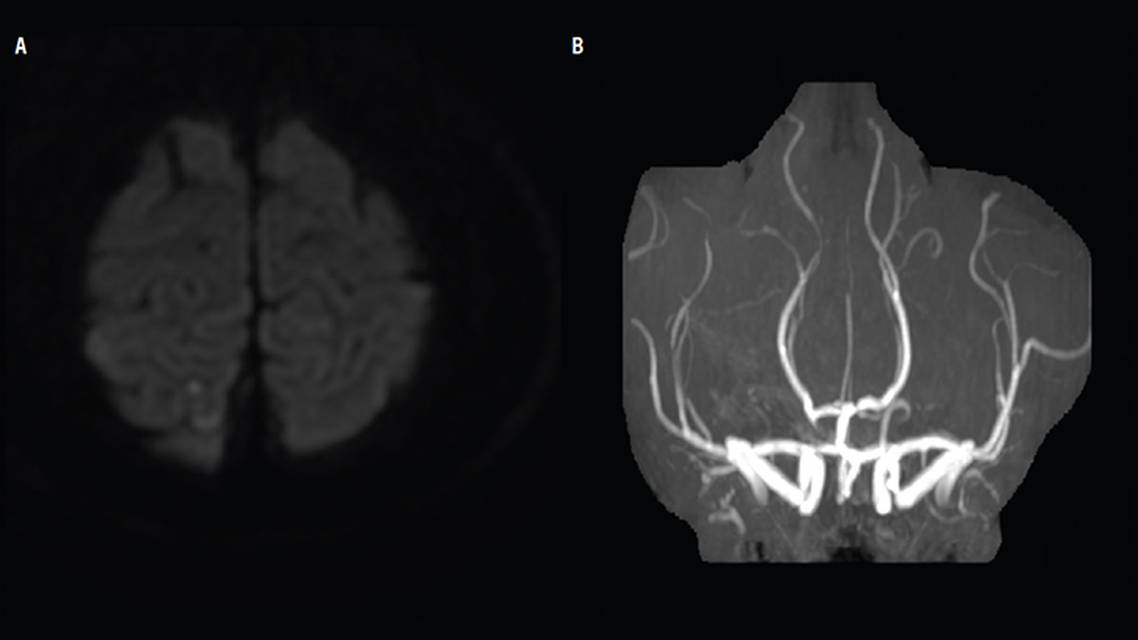

CP had brain MRI and MR angiography that showed no significant abnormalities except a tiny, scattered stroke in the left parietal lobe (Figure 1A) and questionable segmental beading in the distal M1 and M2 segments of the middle cerebral arteries (MCAs; Figure 1B). Transcranial Doppler (TCD) study (Figure 2) showed high mean systolic velocity in both MCA M2 segments with bruit and increased Lindegaard ratio (LR), consistent with moderate vasospasm (mean flow velocity [MFV] right side 145 cm/second, LR: 4; left side 152 cm/second, LR: 5). After the 2 recurrences of thunderclap headache, a cerebral angiogram was performed (Figure 3) and confirmed diffuse vasospasm intracranially.

Although CT and CT angiography are faster to obtain and less prone to motion artifact, MRI and MR angiography are often used to avoid radiation exposure and iodinated contrast. On brain MRI, the presence of hyperintense vessels has been hypothesized to be a biomarker for RCVS because these show abnormal flow in small vessels13 before detection of vasoconstriction.14 MRI is often combined with MR angiography, which has an 80% sensitivity rate for RCVS-related cerebral vasoconstriction,15 similar to CT angiography. In this case, there was a segmental focus on diffusion-weighted imaging (DWI), combined with narrowing and spasm of the posterior and anterior arteries on MR angiography, which are diagnostic for RCVS.